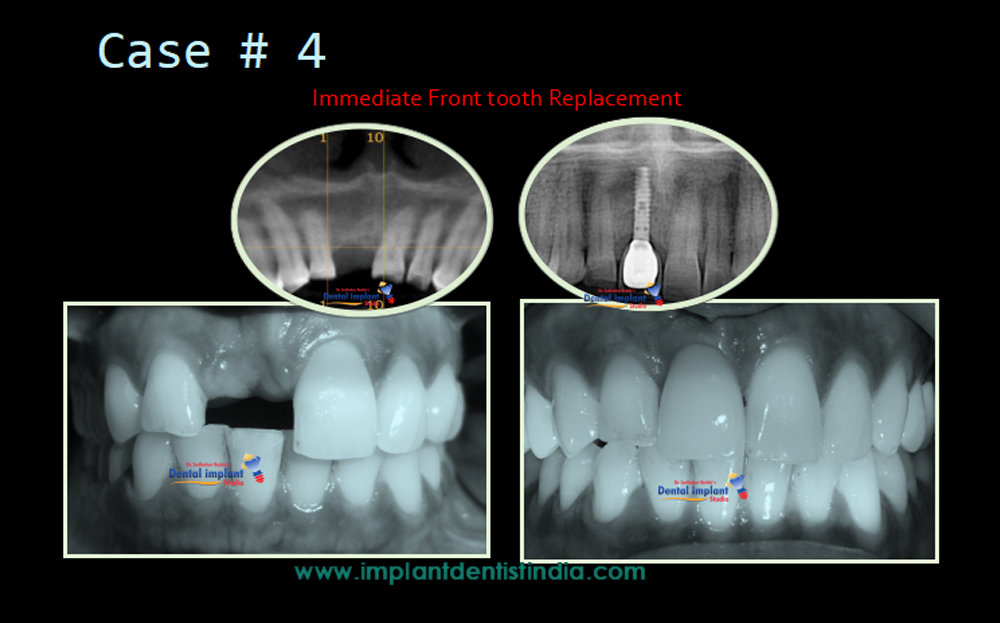

Immediate Front Teeth Replacement with Basal Implants | View Case Series

Patients who lost front teeth due to infection or accidents etc. have no enough bone many times to place regular implants. In such cases, To avoid bone developing surgeries and also avoid 6-8 months of waiting periods , we can do basal implants and give immediate fixed teeth for front area.